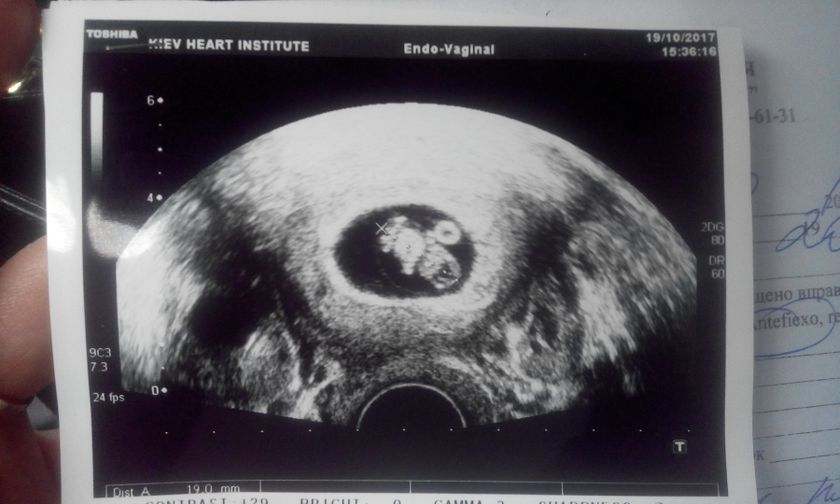

В общем, пришла я к своему любимому врачу, она мне сразу сделала УЗИ и здесь началось самое интересное))) Сказала что мой красавчик растет, лежит удобно, показала мне как стучит сердечко, но к сожалению не послушала, наверное нет там такой возможности. Смотрела на свою кроху и нарадоваться не могла )) сказала что беременность проходит очень даже хорошо)

Написано ктр 19мм)

Спасибо) сказала что 8-9 неделя. Но я точно знаю когда я забеременела так как отслеживала на УЗИ овуляцию и делала укол хгч )

Завтра у меня 9 недель акушерских или 7 недель эмбриональных)))

Ктр 19мм)